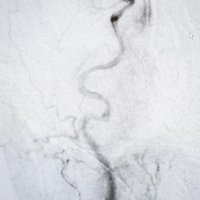

Sam zahvat odvija se otprilike na sljedeći način: nakon što pacijent prođe hitni prijam, neurologa te hitni CT i angiografiju koja pokazuje u kojem dijelu mozga je tromb, bolesniku se kroz arteriju u preponi uvodi dugački kateter, sve do mjesta u mozgu gdje se smjestio tromb. Kroz njega potom prolazi manji mikrokateter kojom se provodi takozvani stent retriever. Kad se oslobodi, on se u sljedećih nekoliko minuta raširi u mrežicu kojom se lovi krvni ugrušak.

Krvna žila potom se zatvori balonom kako krv ne bi otplavila tromb, a stent se povlači u kateter, zajedno s trombom. Postupak se ponavlja sve dok se i posljednji komadić tromba ne izvadi iz krvne žile. Druga metoda uključuje nadovezivanje katetera za aspiraciju. Ona se spaja na crpku koja usisava tromb. Izbor metode ovisi o veličini krvnog ugruška i mjestu na kojem se nalazi.